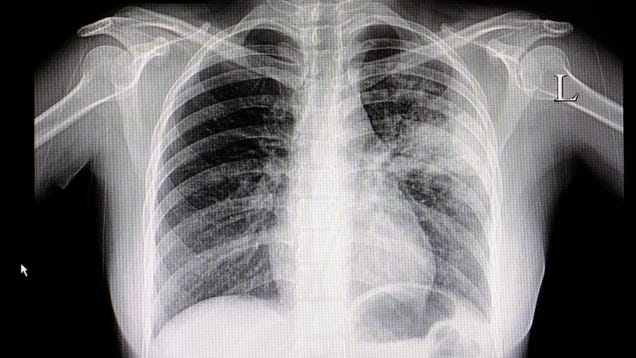

Strange Spike of Child Pneumonia Cases in China Likely Not a Novel Pathogen, Officials Say

An unusual surge of respiratory illness has been plaguing China in recent months, with increased cases of pneumonia affecting children in particular. Despite some early confusion, however, local health officials say these cases are not being caused by a novel germ. Instead, the surge is likely tied to a mix of known…